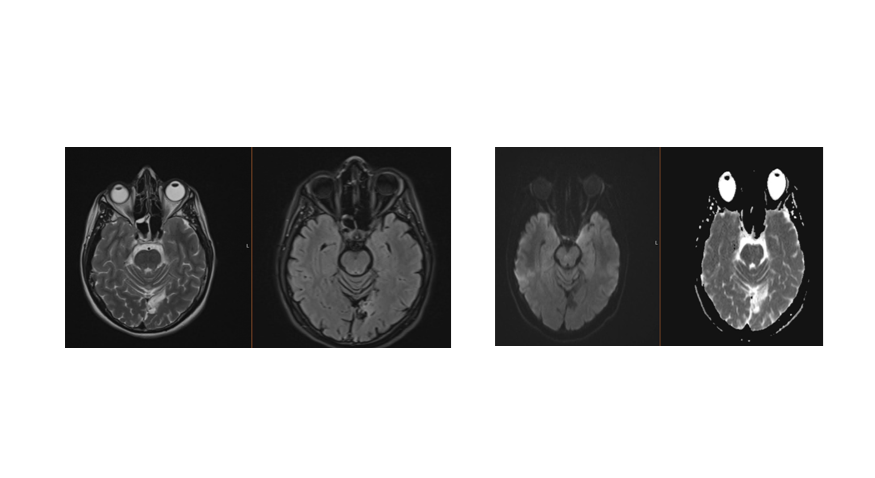

MR mozga: Nalaz pokazuje akutnu ishemijsku leziju u lijevom okcipitalnom području, unutar irigacijskog područja lijeve stražnje cerebralne arterije (ACP).

Diskusija: Ovaj slučaj 33-godišnje pacijentice s dijagnozom komplicirane migrene i desnostranom homonimnom hemianopsijom dodatno potvrđuje vezu između migrene, posebice s aurom, i moždanog udara. Pacijentica nije imala klasične vaskularne čimbenike rizika, osim pušenja, no razvila je moždani udar u stražnjoj cirkulaciji. Prisutnost vizualnih smetnji, trnjenja te glavobolje s neurološkim deficitima su simptomi koji upućuju na migrenu s aurom, a istovremena pojava akutne ishemijske lezije potvrđuje značajan rizik od moždanog udara u ovoj skupini.